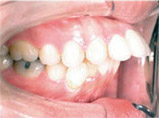

向外暴出

牙齒向外暴出藉由矯正得到適當的改善:

Before

After